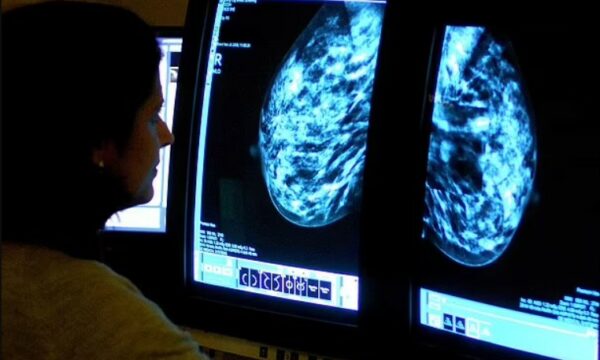

Ndryshim i madh në papteste që do të thotë se deri në shtatë milionë gra do të testohen më rrallë

Zbulim madhor për tumoret e gjirit që janë shumë të vegjël për t’u parë në skanime

Zbulim madhor për kancerin e shkaktuar nga seksi oral – rastet po rritën tek të rinj nën 50 vjeç

Shenjat e fshehura të një kanceri që po rritet më shpejt se kanceri i zorrës së trashë tek të rinjtë

Ndryshim i madh në papteste që do të thotë se deri në shtatë milionë gra do të testohen më rrallë